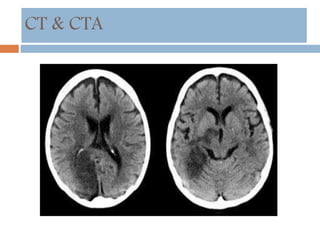

CT & CTA

 Sulci effacement

 Lentiform obscuration